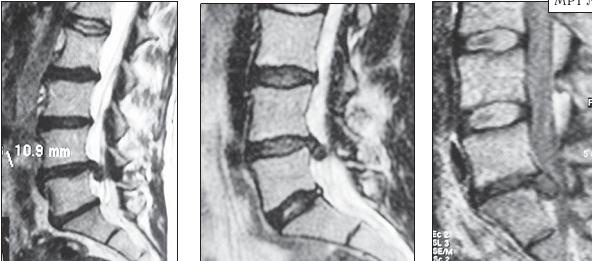

МРТ № 25

На серии снимков МРТ № 25 наблюдаются дорсальные грыжи межпозвонковых дисков в поясничном отделе позвоночника в сегментах LIV-LV Lv—SI Такие комбинации, в которых образуются по нескольку грыж, межпозвонковых дисков одновременно, случаются довольно часто на более поздних стадиях развития дегенеративно-дистрофического процесса. В общем, беда не приходит одна, «несчастье» любит, компанию